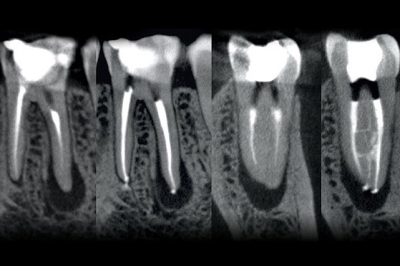

Biolase also received a boost last week, with the US Food & Drugs Administration (FDA) clearing its new “EdgePRO” laser microfluidic irrigation device for use by endodontists - dentists specializing in the internal structures of teeth, for example root canal treatment.

The microfluidic irrigation device is intended for use with Biolase’s Er,Cr:YSGG laser technology, which operates at a wavelength of 2780 nm.

Video: EdgePRO laser microfluidic irrigation for root canal treatment: